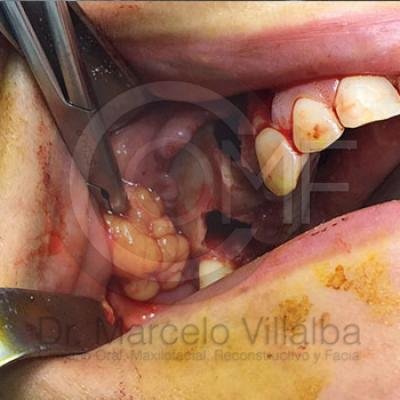

Comunicación en Seno Maxilar

Comunicacion Seno Maxilar 3